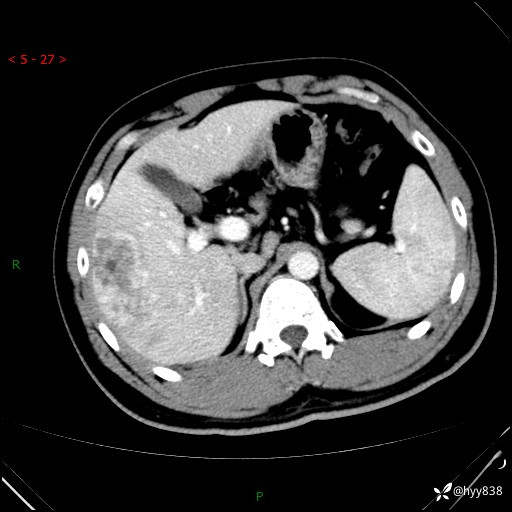

增强动脉期

img